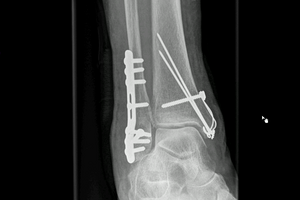

Eine Operation ist aber in den meisten Fällen notwendig, da häufig eine starke Verschiebung der Fraktur vorliegt. Die Operation erfolgt in der Regel zeitversetzt nach Abschwellung des Sprunggelenks. Bis dahin erfolgt eine Ruhigstellung im Gips und konsequente Hochlagerung und Kühlung (ambulant oder stationär). Ziel der Operation ist es, die verschobenen Fragmente und das Gelenk zu rekonstruieren. In Abhängigkeit von der Fraktur erfolgt eine Stabilisierung mit Platten und/oder Schrauben. Neben einer Verletzung der Knochen kann auch eine Verletzung der Bänder vorliegen. Die Stabilität des Sprunggelenks muss daher während der Operation getestet werden. Sollte eine Instabilität der Bänder oder der Syndesmose vorliegen, so werden diese mit behandelt.